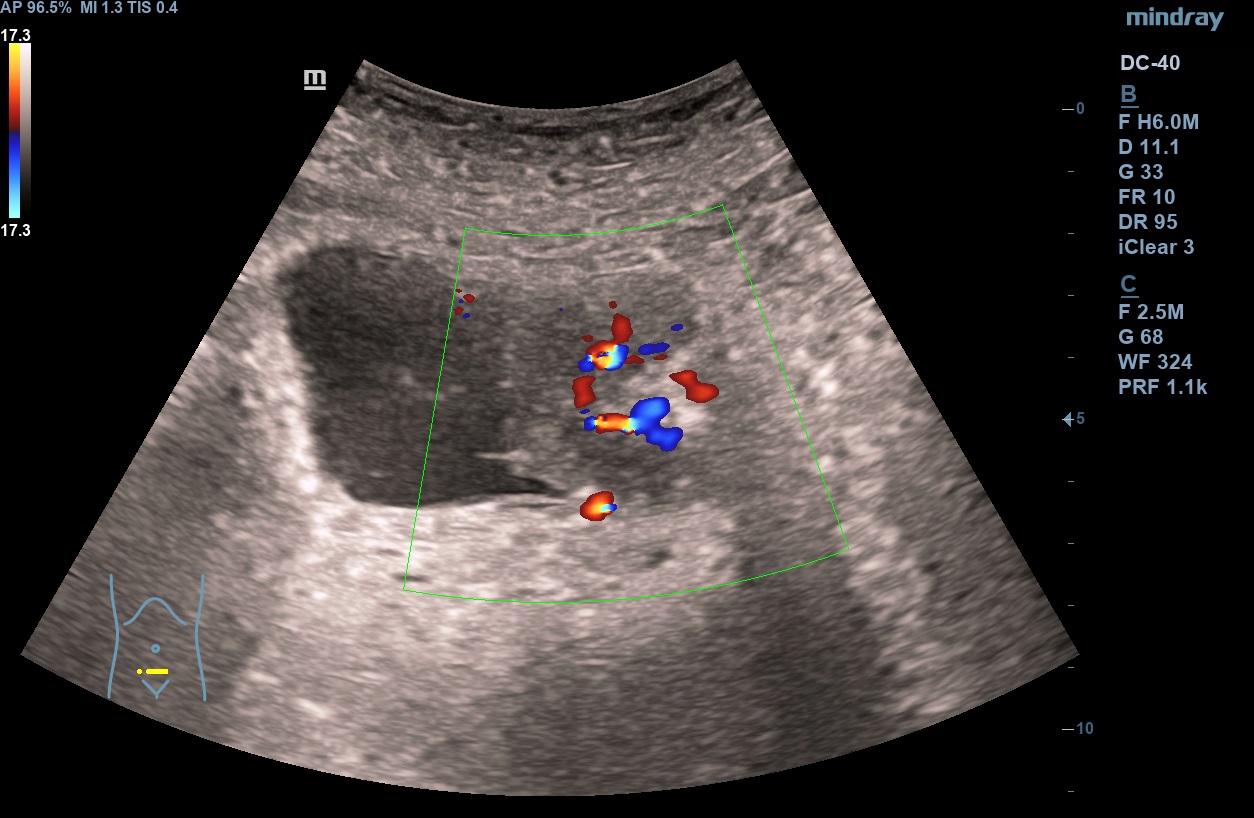

Hallazgos ecográficos

En analítica de control por Cardiología se evidencia anemia microcítica hipocrómica. En el estudio de la misma y concomitando con una infección de orina, se objetiva microhematuria, si bien no reseñable. Se trata la infección de orina y dada la desaparición de la sintomatología y la buena respuesta a tratamiento con ferroterapia, se cesa el estudio. Repite en dos ocasiones más ITU + microhematuria. Dada la continuidad de los episodios, realizamos ecografía en AP objetivando la presencia de una LOE intravesical, que se estudia en el ámbito hospitalario confirmado el diagnóstico de ca. uroterial.

Ecografía en AP: sospecha de tumoración intravesical. TAC abdómino pélvico: masa vesical dependiente de pared izquierda con hipercaptación, impresiona de diseminación a distancia. Uro-TC confirma ca. de vejiga. AP con carcinoma uroterial papilar de alto grado G3pT1. Estudio de extensión por el momento negativo.